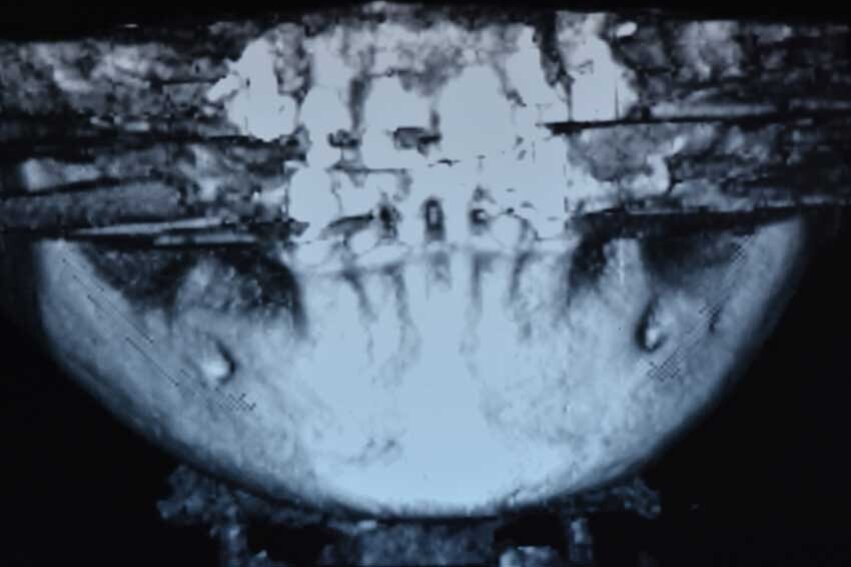

La CBCT dell’arcata inferiore evidenziava una cresta ossea edentula molto riassorbita in senso orizzontale con uno spessore medio non superiore ai 3 mm (Figg. 1b, 1c). Dopo una preventiva seduta di igiene orale veniva programmato un intervento di rigenerazione ossea con ausilio della tecnica della lamina corticale (Fig. 2).

Dopo aver somministrato l’anestesia locale con Articaina con adrenalina 1.200.00 veniva eseguita un’incisone con lama 12 sulla cresta edentula facendo attenzione a dividere l’esigua quantità di gengiva cheratinizzata in maniera equa tra i due lembi, vestibolare e linguale. La cresta esposta confermava quanto osservato sulla CBCT, lo spessore in cresta era di 3 mm nella zona distale al canino e andava ad assottigliarsi fino ad 1 mm nella zona dei molari. In prossimità del sito 46 si trovava un residuo radicolare, che veniva rimosso e nella stessa posizione veniva inserito un impianto di diametro standard (4 mm) mentre gli impianti nei siti dei premolari e del secondo molare erano di diametro ridotto (3.5) (Fig. 4).